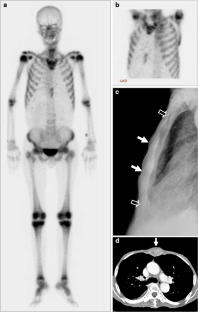

Absent Sternum as the First Manifestation of Bone Metastasis on Bone Scintigraphy

The sternum is known as a relatively common site for bone metastases by a variety of malignant neoplasms. The usual finding is increased radiotracer uptake on bone scintigraphy, and cold metastasis is distinctly unusual. In addition, total nonvisualization of the sternum presenting as bone metastasis is extremely rare. We describe two cases with similar findings (absent sternum showing no activity of the sternal segments on bone scintigraphy), which corresponded to metastatic involvement. These findings were shown to be the first manifestation of hepatocellular carcinoma in one patient and bone metastasis in another patient with ovarian cancer.

Fig. 2